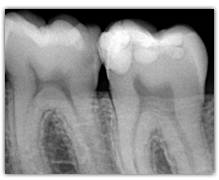

What represent the white, blue, red or black areas which can been seen on the tooth?

According to the pathologies of the tooth (destructured enamel, affected dentine, anfractuous fissure, presence of a crown…), the signal of fluorescence of the dentine will be different (weaker, darker, redder, absent…)

Does SOPROLIFE generates « False alerts »?

When SOPROLIFE generates a red fluorescence in a fissure, it is either due to a caries or to organic deposits. In this case a cleaning (pounce bag, air abrasion linked to Na bicarbonate ) is advised only in the suspicious fissure in order to avoid a falser alert.

Why is the tooth green on the screen?

The spectrum of the signal of fluorescence (let’s call it "its color") is rather in the green when the dentine is healthy and red/dark when the dentine is infected.